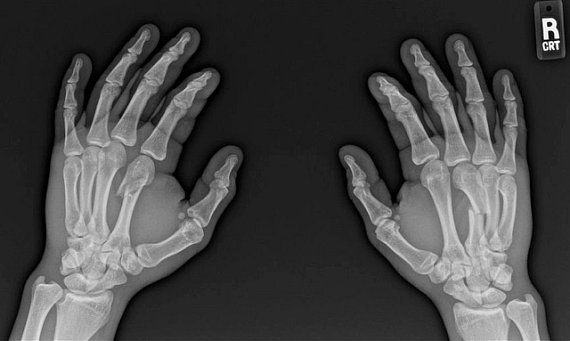

Jean Silva Shares X-Rays of Broken Hands Sustained in Drew Dober Fight

Let the record show that Ultimate Fighting Championship up-and-comer Jean Silva is tough beyond words.